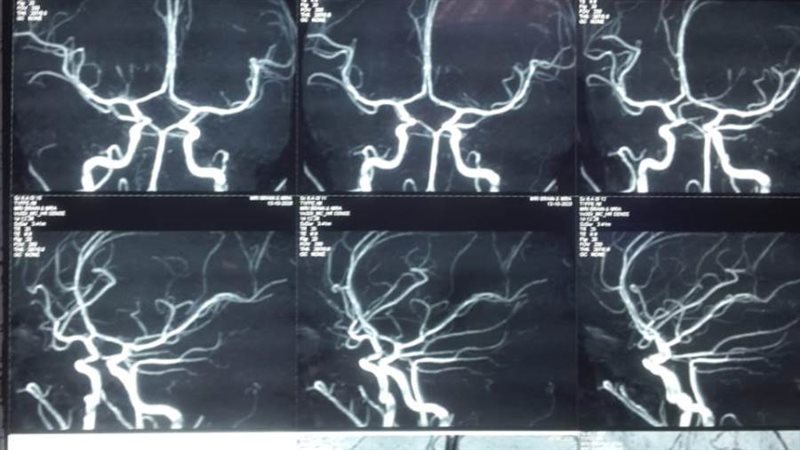

وكان المستشفى استقبل طفلة تبلغ من العمر 11 عاما، تعاني من نزيف ببطينات المخ أدى إلى تدهور شديد فى درجة الوعي لارتفاع ضغط السائل النخاعي على جذع المخ، وتم التدخل الجراحي العاجل من الفريق الطبي، وعمل الجراحة بطريقة بسيطة باستخدام جهاز ( CVP)، وتحويل مسار السائل تحت فروة الرأس ventricluosubgaleal shunting.